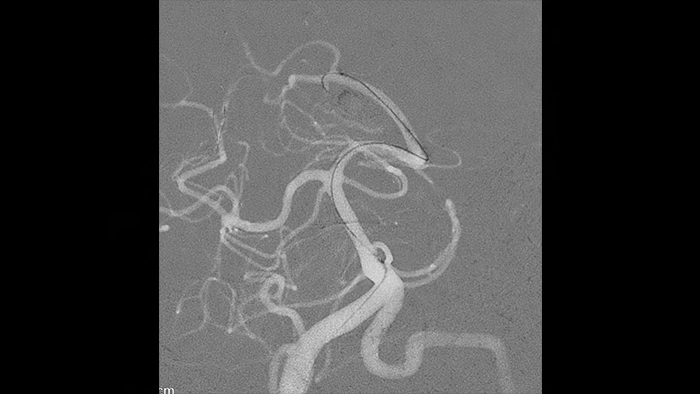

The Roadmap Pro glue mode filters out already embolized vessels, allowing you to focus on what you are injecting and how it is diffusing.